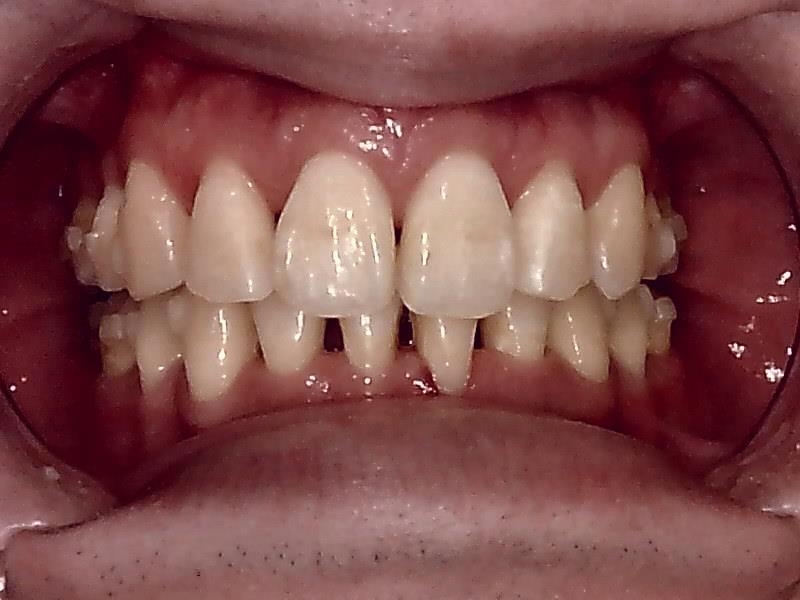

術前口腔内写真 正面観

スマイルラインも美しくなり、前突した歯も改善され噛み合わせもしっかり正常に戻しました。

○前歯の前突した歯を治したい

○八の字型の歯並びを改善したい

○笑った時の歯のアーチを綺麗にしたい